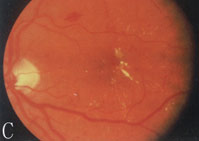

【影像表現】

CT:

1.兩側多條眼外肌增粗,以下直肌和內直肌最多見。

2.其特徵為肌腹部呈梭形肥大,而肌腱處正常。

3.單一下直肌肥大的患者,CT橫軸位掃描顯示肌錐內軟組織腫塊影,易誤診為眶尖腫瘤,結合冠狀位掃描有助於診斷。

4.眶內脂肪增多表現為球後間隙異常清晰,眶隔前移。

5.增強掃描見增粗的眼外肌有明顯的強化。

6.鑑別診斷炎性假瘤多為單側發病,無性別差異,肌腱、肌腹均增大,眼肌附著處的眼環也見受累。

MRI:可多角度成像顯示眼外肌受累情況。